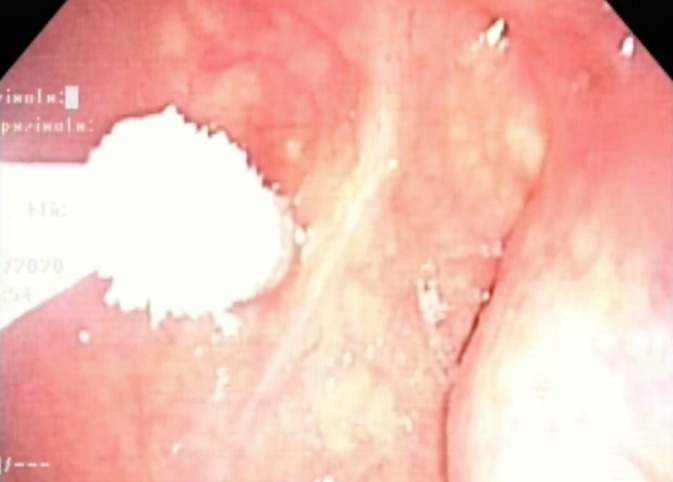

FIGURE 3.

Endoscopic view of the swab on the posterior wall of the nasopharynx [Color figure can be viewed at wileyonlinelibrary.com]

The patient wears a surgical mask. She is informed about the procedure that is about to be performed. The patient must be seated in a comfortable position with his head resting on the back of the chair. The patient's head must be placed on a horizontal plane parallel to the floor. The patient is asked to lower the mask by uncovering only her nose and keeping the mouth closed. After opening the swab in a sterile manner, the operator positions the patient laterally in order to avoid direct droplets from sneezing or coughing. The swab is inserted gently into the nostril. The insertion must be parallel to the floor of the nasal fossa. The swab is kept medial and facing the nasal septum (do not insert the swab upward, as in this case the swab stops at the level of the nasal turbinates and the viral RNA sampling may not be significant). It is important to use the mark on the swab stick as a depth reference (Figure 2). However, when the operator feels an obstacle to further introduction, it means that the swab will have reached the posterior wall of the nasopharynx. With clockwise and counterclockwise movement, repeatedly rub the swab against the posterior wall of the nasopharynx (Figure 3), for about 10 to 15 seconds. Extract the swab from the nostril taking care not to contaminate it upon exit, introduce it into the test tube and break it at the mark on the stick. In case of difficulty in introducing the swab into a nasal fossa due to deviation of the nasal septum or hypertrophy of the inferior turbinates, proceed with the same technique in the contralateral nasal fossa. The endoscopic vision shown in the video has a didactic purpose only; the nasopharyngeal swab should not be performed with the aid of the endoscope.